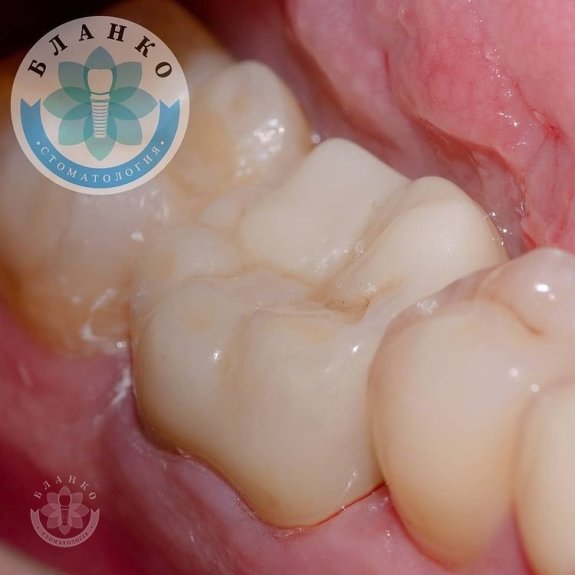

- знято відбитки та виготовлено високоміцну, гіпоалергенну та високоестетичну коронку з діоксиду цирконію.

✳️Разом, ми спостерігаємо цікаву ситуацію.

На прикладі цього клінічного випадку ми чітко бачимо, що заощаджувати на своєму здоров'ї небажано, бо зуб не туфель, в урну не викинеш.